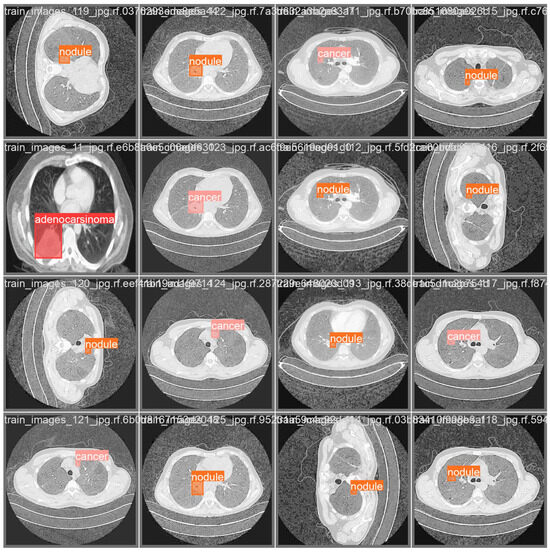

- Adenocarcinoma (Blue Line):

- -

- The blue line represents the precision–recall relationship for the adenocarcinoma class.

- With an average precision (AP) of 0.734, the model performs relatively well in detecting adenocarcinoma, maintaining high precision and recall values.

- Cancer (Orange Line):

- The orange line represents the performance for the cancer class.

- An AP of 0.588 indicates moderate performance, with a noticeable drop in precision as recall increases, suggesting that the model struggles more with this class compared to adenocarcinoma and nodules.

- Nodule (Green Line):

- The green line shows the precision–recall for nodules.

- With the highest AP of 0.802, the model performs best on this class, indicating high precision and recall across most thresholds.

- All Classes (Bold Blue Line):

- The bold blue line represents the overall performance across all classes, with an mAP@0.5 of 0.708.

- The mean average precision (mAP) at an IoU threshold of 0.5 provides a single metric summarizing the model’s performance across all classes.

- An mAP@0.5 of 0.708 suggests that the model has a strong overall detection capability, balancing precision and recall well.